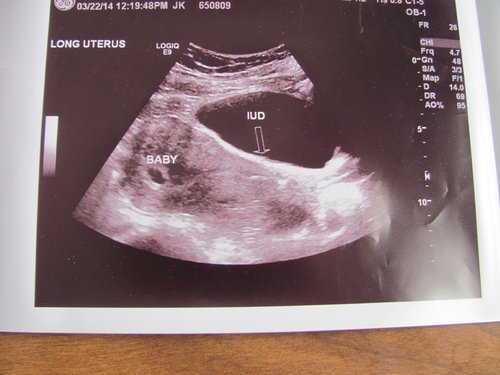

Have had an iud for 6yrs found out it migrated and SUPRISE! We have a baby! This will be #6 for us!

They are unable to remove it because of its location miscarriage risk is high throughout the entire pregnancy.

• I am so glad they couldn't find yours. Even though all of it is freaky I am thankful mine is a para guard and non hormonal. It is definitely in their all u see is a big white line blocking baby view during U/S. But we did get a heart beat of 150 at 7w5d and everything looked good otherwise. We go back on the 16th for another U/S and again two weeks after that. The biggest worry after 12w is PROM. I feel much happier today I think I was really just having a rock bottom down moment last night thanks for all the T&P

• I found out 3 weeks ago I am pregnant and was on the MIrena IUD. I went to the ER thinking all the cramping I was having was due to cysts. Well the doctor found 2 huge cyst on my right ovary and also showed me that my IUD had slipped down into my cervix then he showed me a Baby with a beautiful heartbeat of 120 I was 6 weeks and 5 days.  I got the IUD removed 2 days later when I was 7 weeks they told me I would cramp and Bleed for about 2 weeks but thank god I havent had any bleeding. I went last monday at 9 weeks and everything looks great! Baby was growing on tract and heartbeat was strong at 176. I would love to stay in touch since I know NOBODY in this situation!!! My youngest just turned 1 I still am in shock but I am also SO IN LOVE WITH THIS BABY and consider it a complete miracle!!! Good luck with your pregnancy! Here my first ultrasound picture